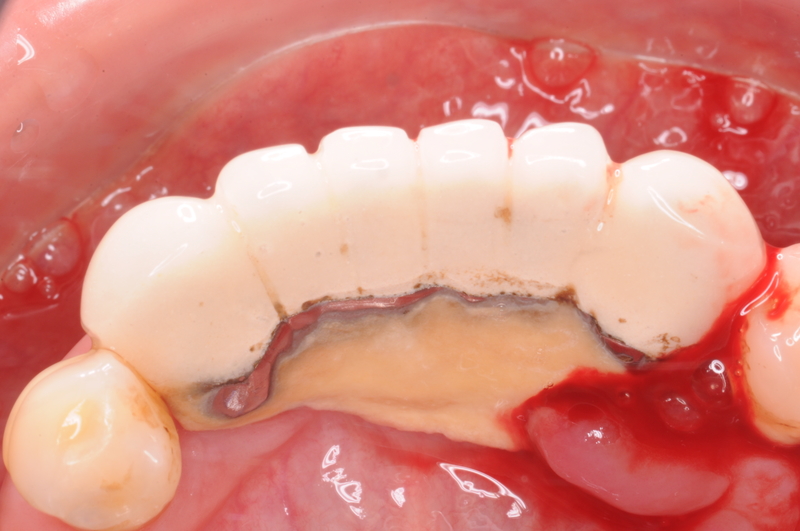

照片上黃黃的那片就是那恐怖的牙結石啊!但這位患者總是流浪在各牙醫診所。